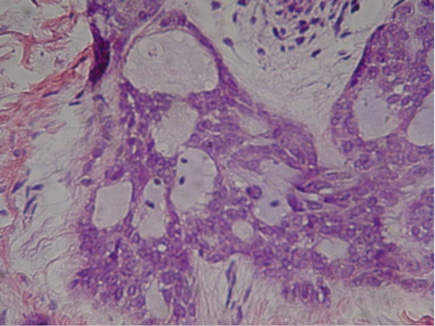

Microscopically, a proliferation of pleomorphic epithelial cells was observed, with abundant cytoplasm, a hyperchromatic nucleus, apparent nucleoli, as well as individual and group keratinizations and high mitotic activity, which infiltrated the underlying connective tissue (Fig. 2).

The diagnosis was then decided as well-differentiated squamous cell carcinoma.

Fig. 2 Microscopic features: proliferation of pleomorphic epithelial cells